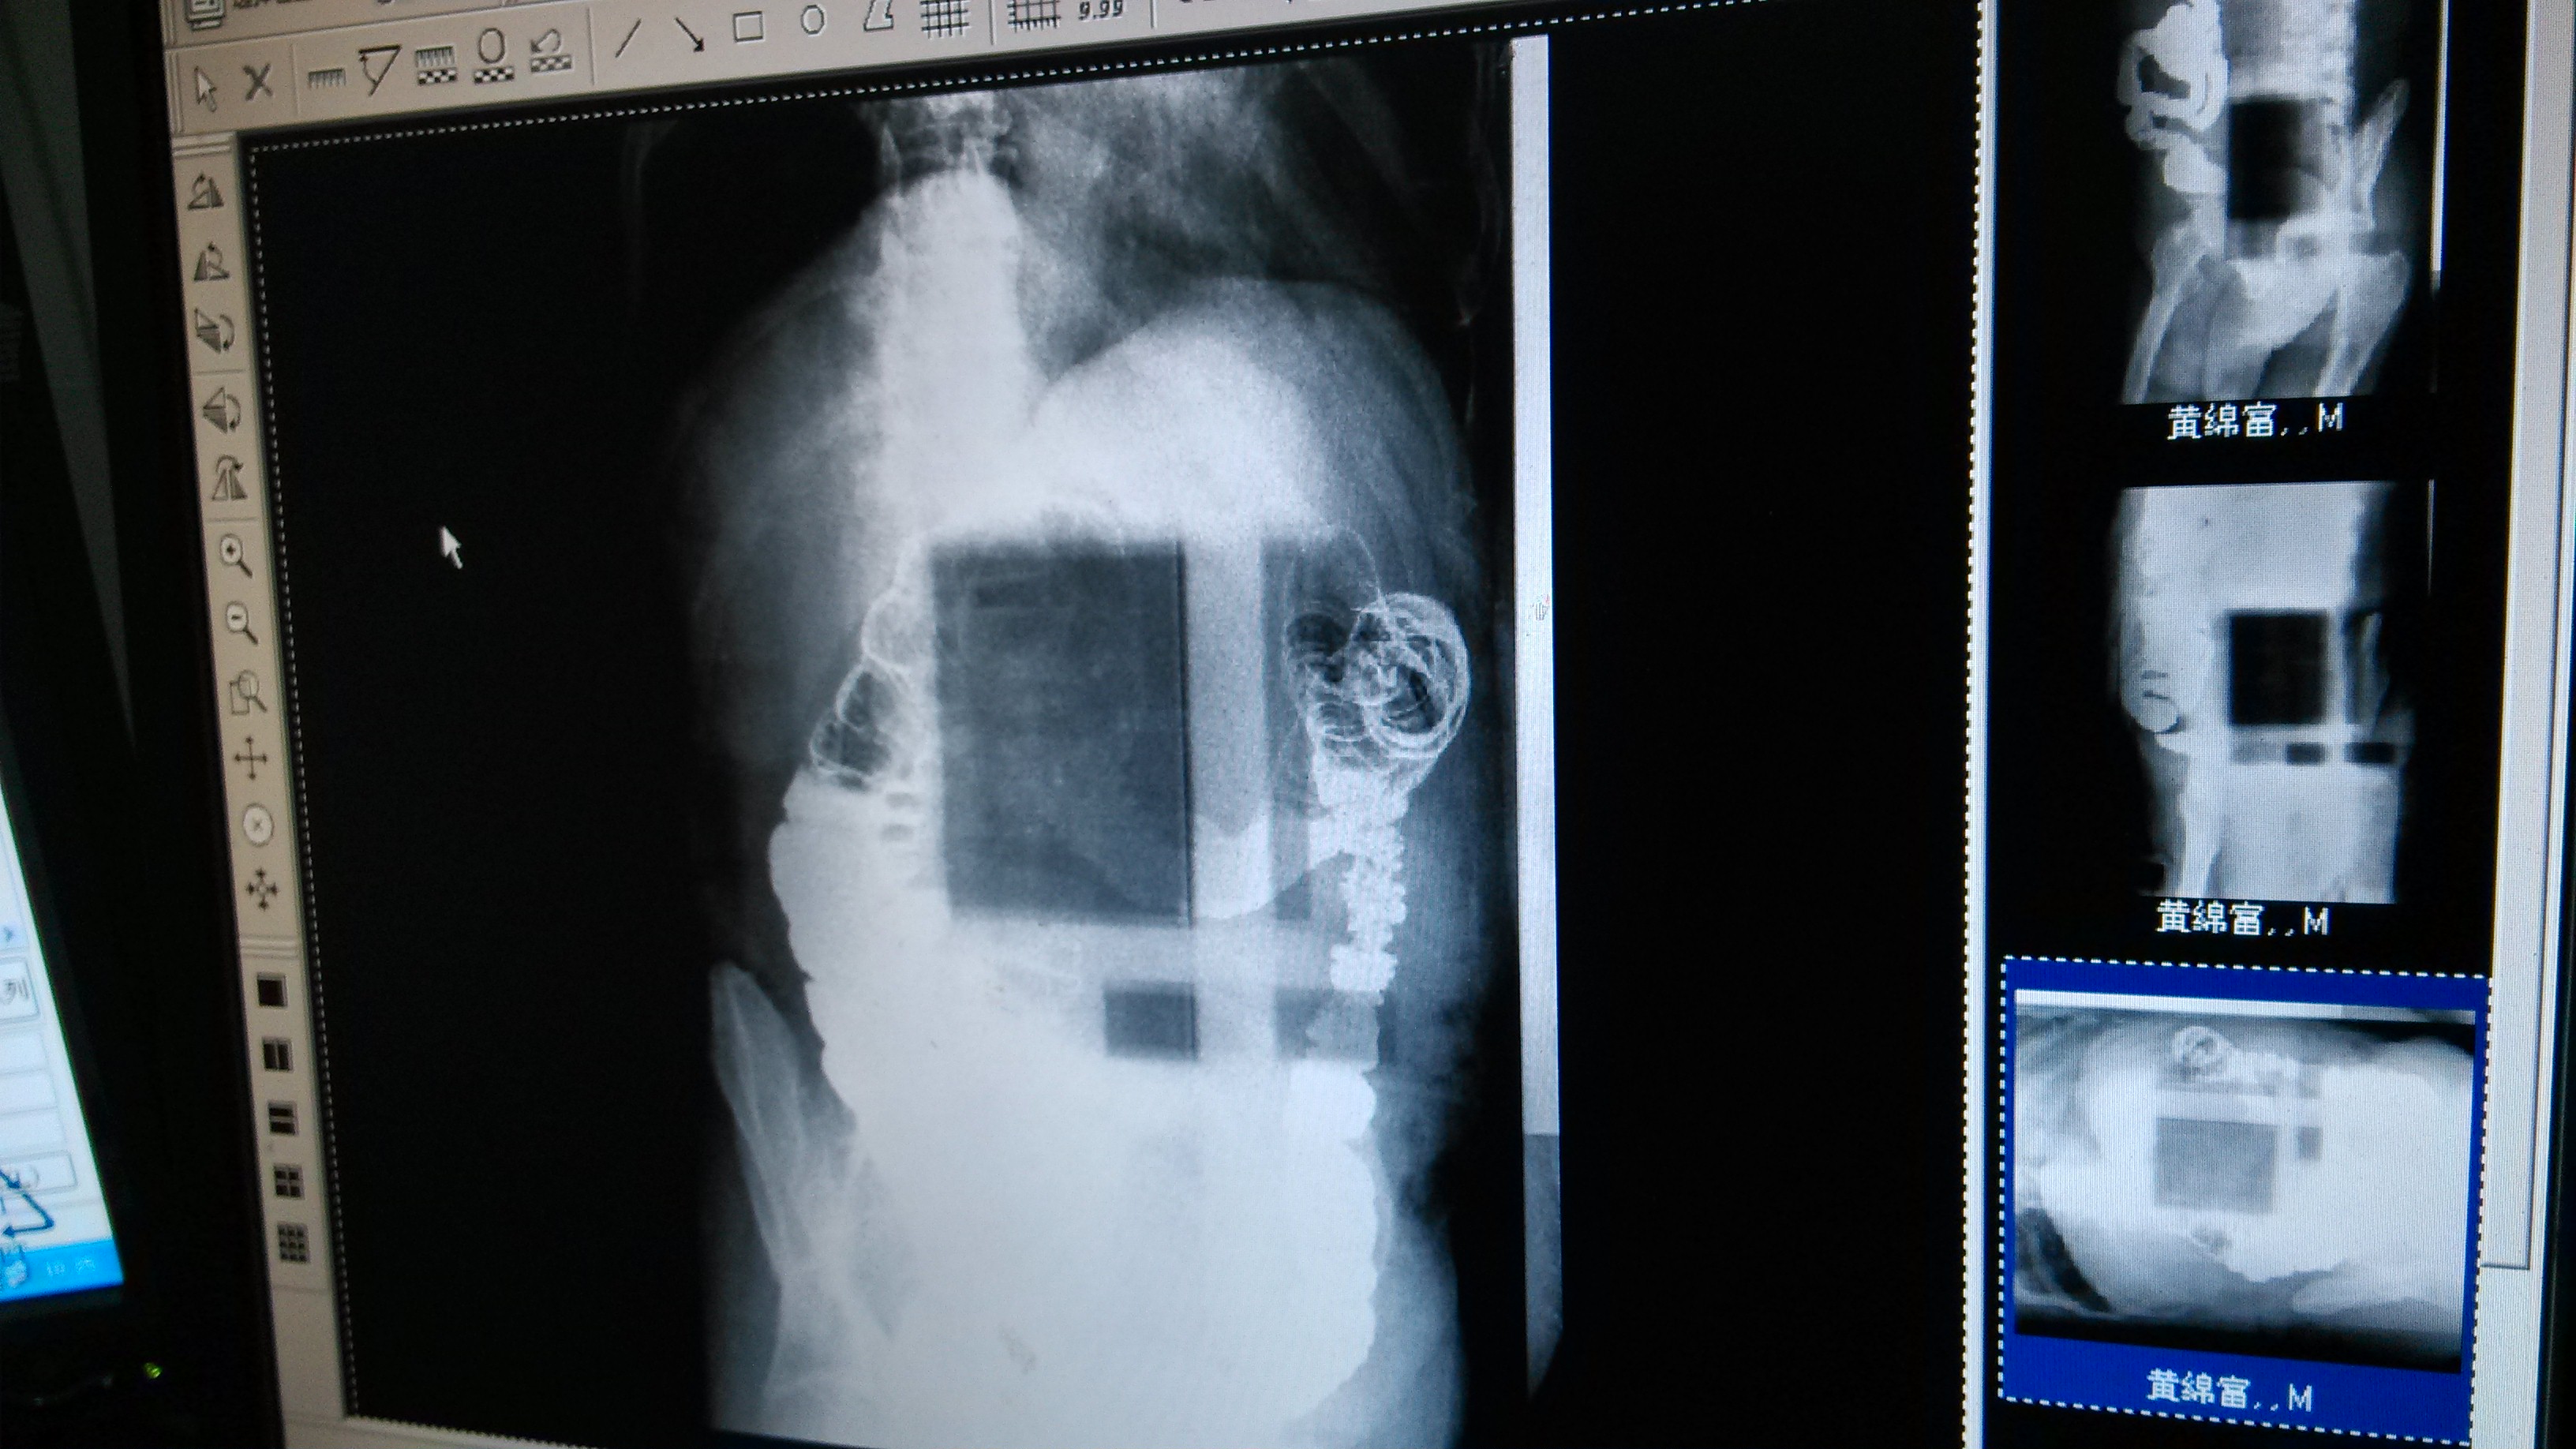

[设备故障求助] 东软1000MA胃肠机故障寻求解答

三个图 拍腹部片子的时候噪点太多根本就看不清

一个是 时常出现方格的阴影  但不是虑线板的问题

从图片上看,1曝光条件不太合适,2探测器好像有坏线。如果说的不对,还望高手赐教,谢谢。

我看你第2,5张图片,你别怀疑别的,影像增强管换了就好。

我遇到过这种故障,换影像增强管后一切OK。100%